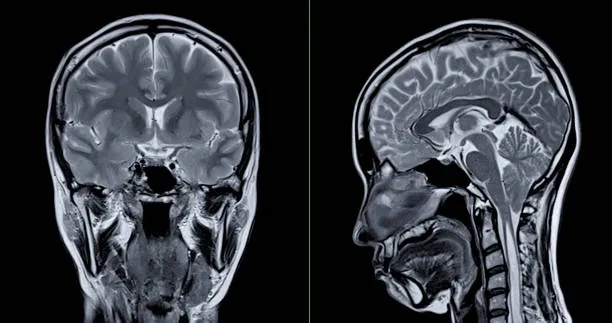

Visualizing concepts related to CTE